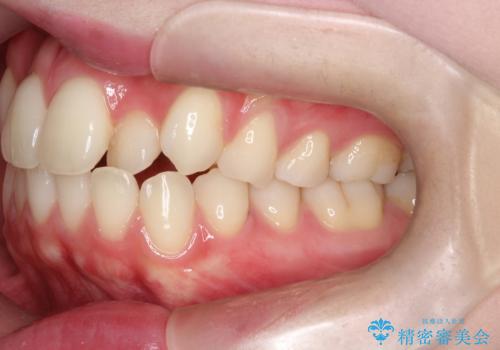

上下4本の抜歯と審美ワイヤー矯正で整った歯並びへ

- 患者様は、歯並びの乱れを整えたいとのことで来院されました。診察の結果、歯列のスペース不足が原因で前歯のガタつきが目立ち、噛み合わせにも影響が出ている状態でした。歯を正しく並べるためにはスペースの確保が必要と判断し、上下の小臼歯4本を抜歯して、審美ワイヤー矯正(白いワイヤーと透明ブラケット)で治療を行う計画を立てました。

まず、抜歯によって歯を動かすためのスペースを確保。その後、審美ワイヤー矯正を用いて、前歯のガタつきを整えながら、噛み合わせの調整も行いました。審美装置を使用することで、矯正中も目立ちにくく、自然な仕上がりを目指して治療を進めました。治療の結果、歯並びがきれいに整い、口元のバランスも改善しました。患者様からは「歯並びがきれいになり、自信を持って笑えるようになった」と喜びの声をいただきました。